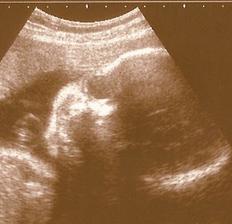

Naše milá rozrůstající se rodinka :o))

Začalo to v dubnu 1999 a zpečetili jsme to nejdříve narozením našeho syna Adámka a poté svatbou 1.10.2005, za chvíli budeme mít první výročí 🙂